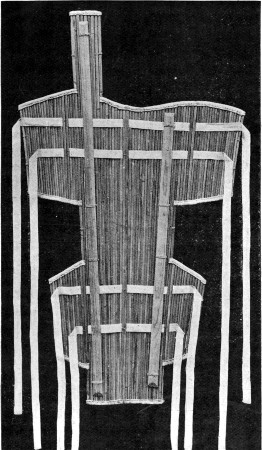

54. Wire Gauze Splint 187

56. Cane Field Splint for Lower Extremity 209

58. Cane Field Splint for Leg 222